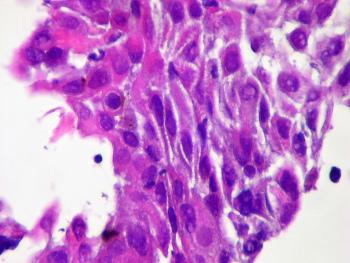

При гистопатологическом исследовании данный тип рака аналогичен злокачественной опухоли тела матки, при этом проявляются свойства ороговевшего или неороговевшего рака. Клетки опухоли значительно отличаются по таким характеристикам, как размер, форма, степень созревания. Клеточные границы не всегда четко прослеживаются. Форма клеток преимущественно полигональная или овальная.

Опухоль образуют клетки, имеющие светлую цитоплазму, поэтому при лабораторном исследовании прослеживаются светлые полосы в очаге поражения. Некоторые опухоли состоят из кист, покрытых плоскими, цилиндрическими клетками, гвоздевидными клетками, у которых ядра похожи на луковицы.